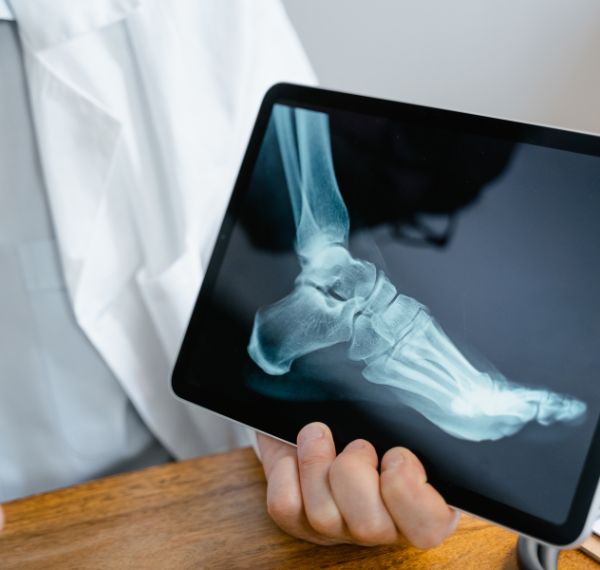

Foot and Ankle Surgery

Surgical solutions for structural or traumatic foot/ankle issues.

Who it’s for: Patients with arthritis, fractures, or deformities.

Key Benefits: Restores foot mechanics, relieves pain, and supports balance.